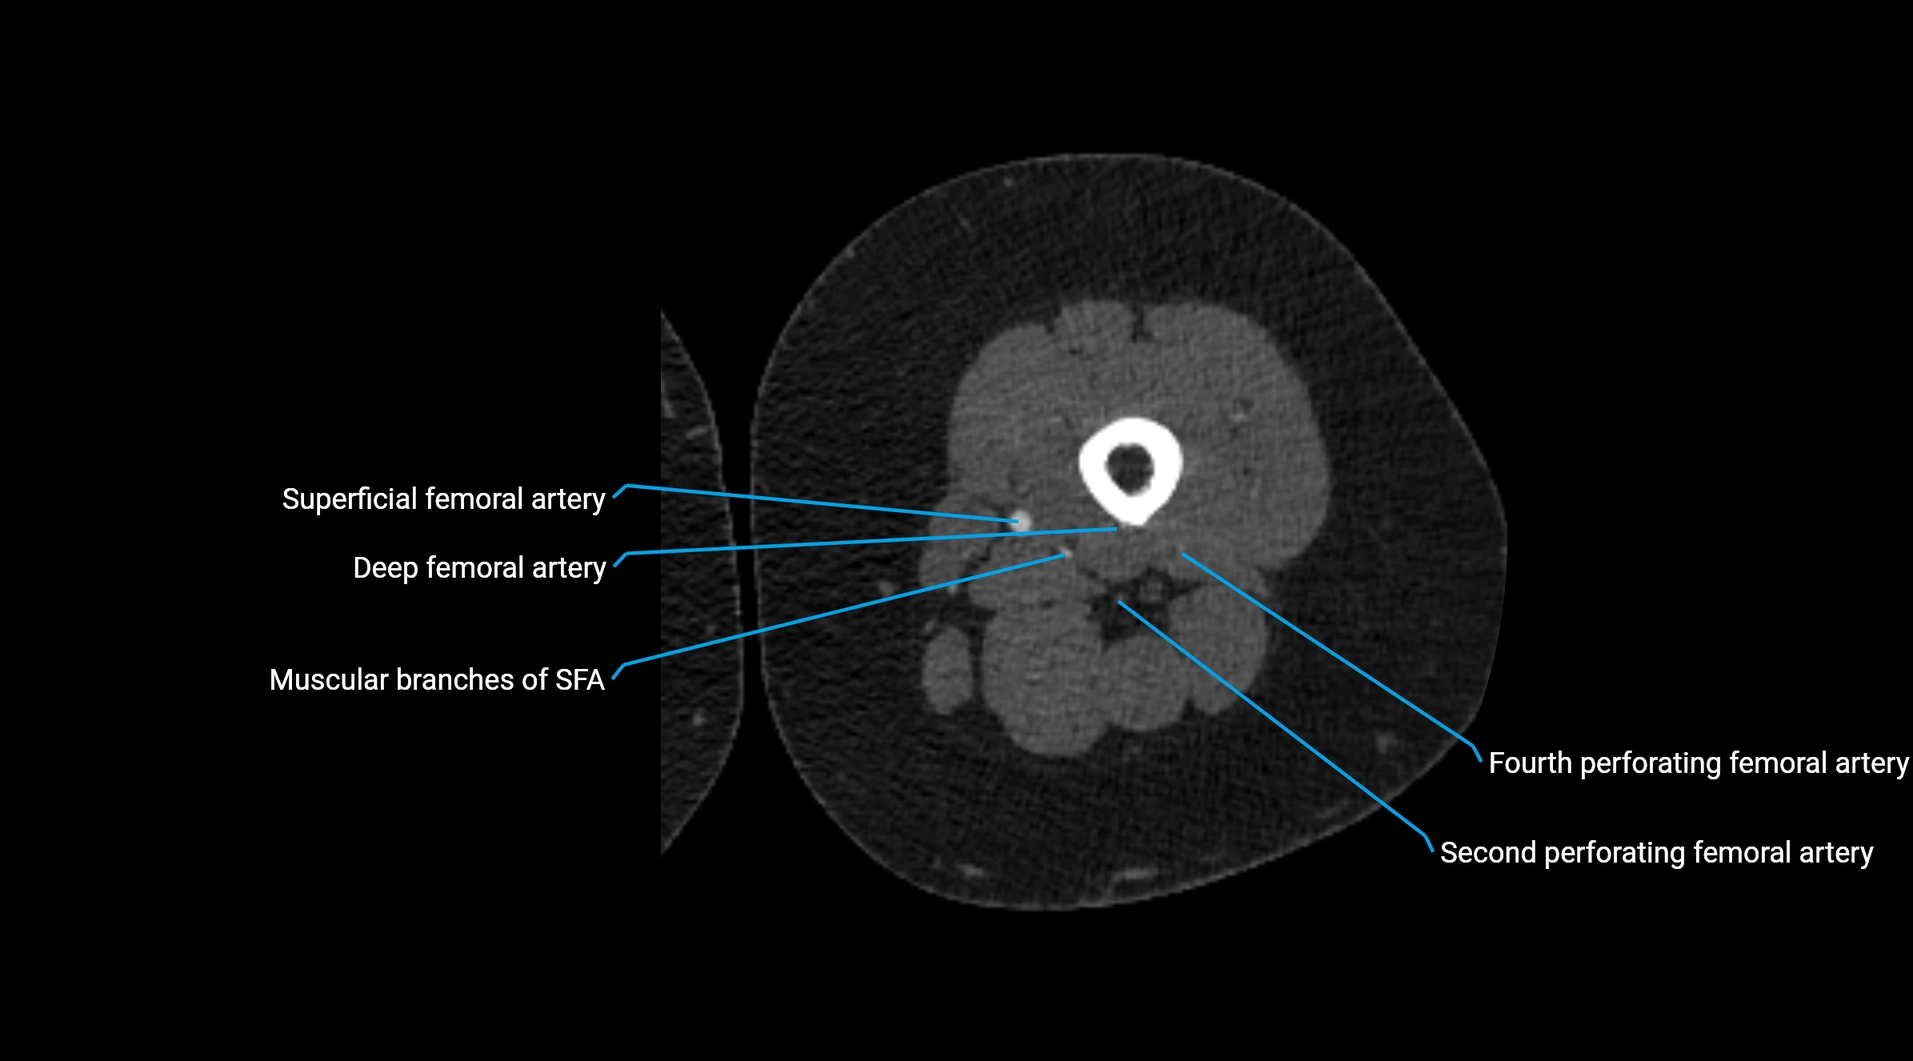

CT images

image